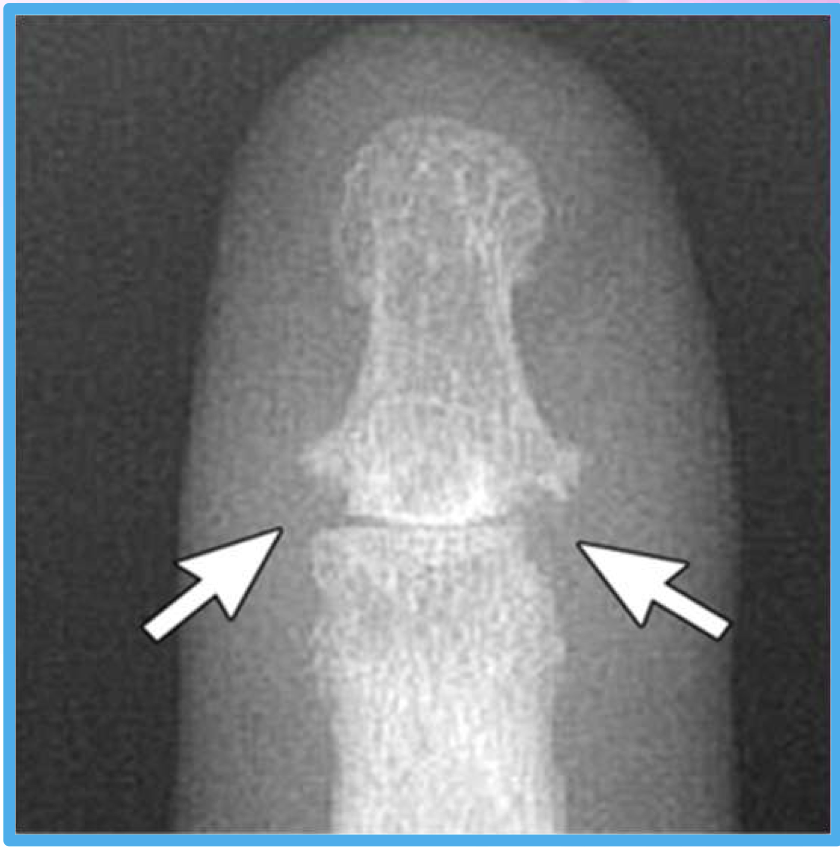

What two findings of PsA are found in this image

periostitis (mouse ears) - lifts periosteum

soft tissue edema - leaves bone density alone

How are the erosions mentioned in the question beforehand different from RA

In RA… don’t lift periosteum, decrease bone density, goes wherever it wants